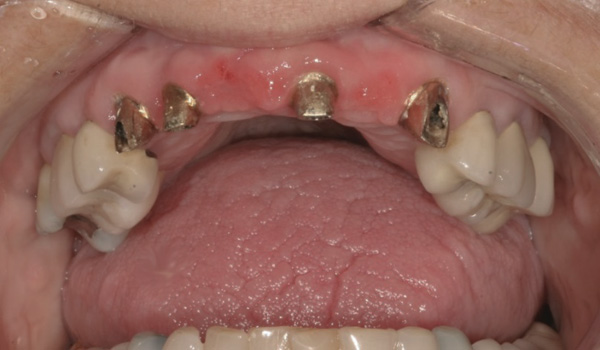

Results: A decision was made to re-prepare all of the abutments intraorally (Figure 3) so that all abutment margins would be at or below the gingival margin. (Of note, tooth Nos. 8 and 9, also shown in Figure 3, were later submerged for the case to be fully implant-supported.) While re-preparation greatly improved the esthetics of the final result, it required retraction cord placement, new impressions, and new castings.

(Note: A separate but similar type of case shown in Figure 4 and Figure 5 further illustrates intraoral abutment re-preparation.)

Figure 3 Abutments re-prepared intraorally.

Figure 3

Figure 4 Following osseointegration of an implant at No. 12, recession was observed at the fixture-level impression stage of No. 13; it was decided to re-prepare the margins of the CAD/CAM custom abutment of implant No. 12. Retraction cord was placed prior to preparation to avoid tissue injury and improve visibility of both tooth No. 11 and the implant custom abutment margin. As expected, recession was greater along the distal side of abutment No. 12, adjacent to the healed extraction/newer implant site.

Figure 4